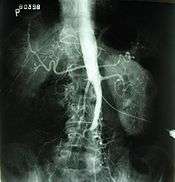

Aortoiliac occlusive disease

Plate from Gray's Anatomy showing the abdominal aorta and the common iliac arteries. | |

In medicine, aortoiliac occlusive disease, also known as Leriche's syndrome and Leriche syndrome, is a form of peripheral artery disease involving the blockage of the abdominal aorta as it transitions into the common iliac arteries.